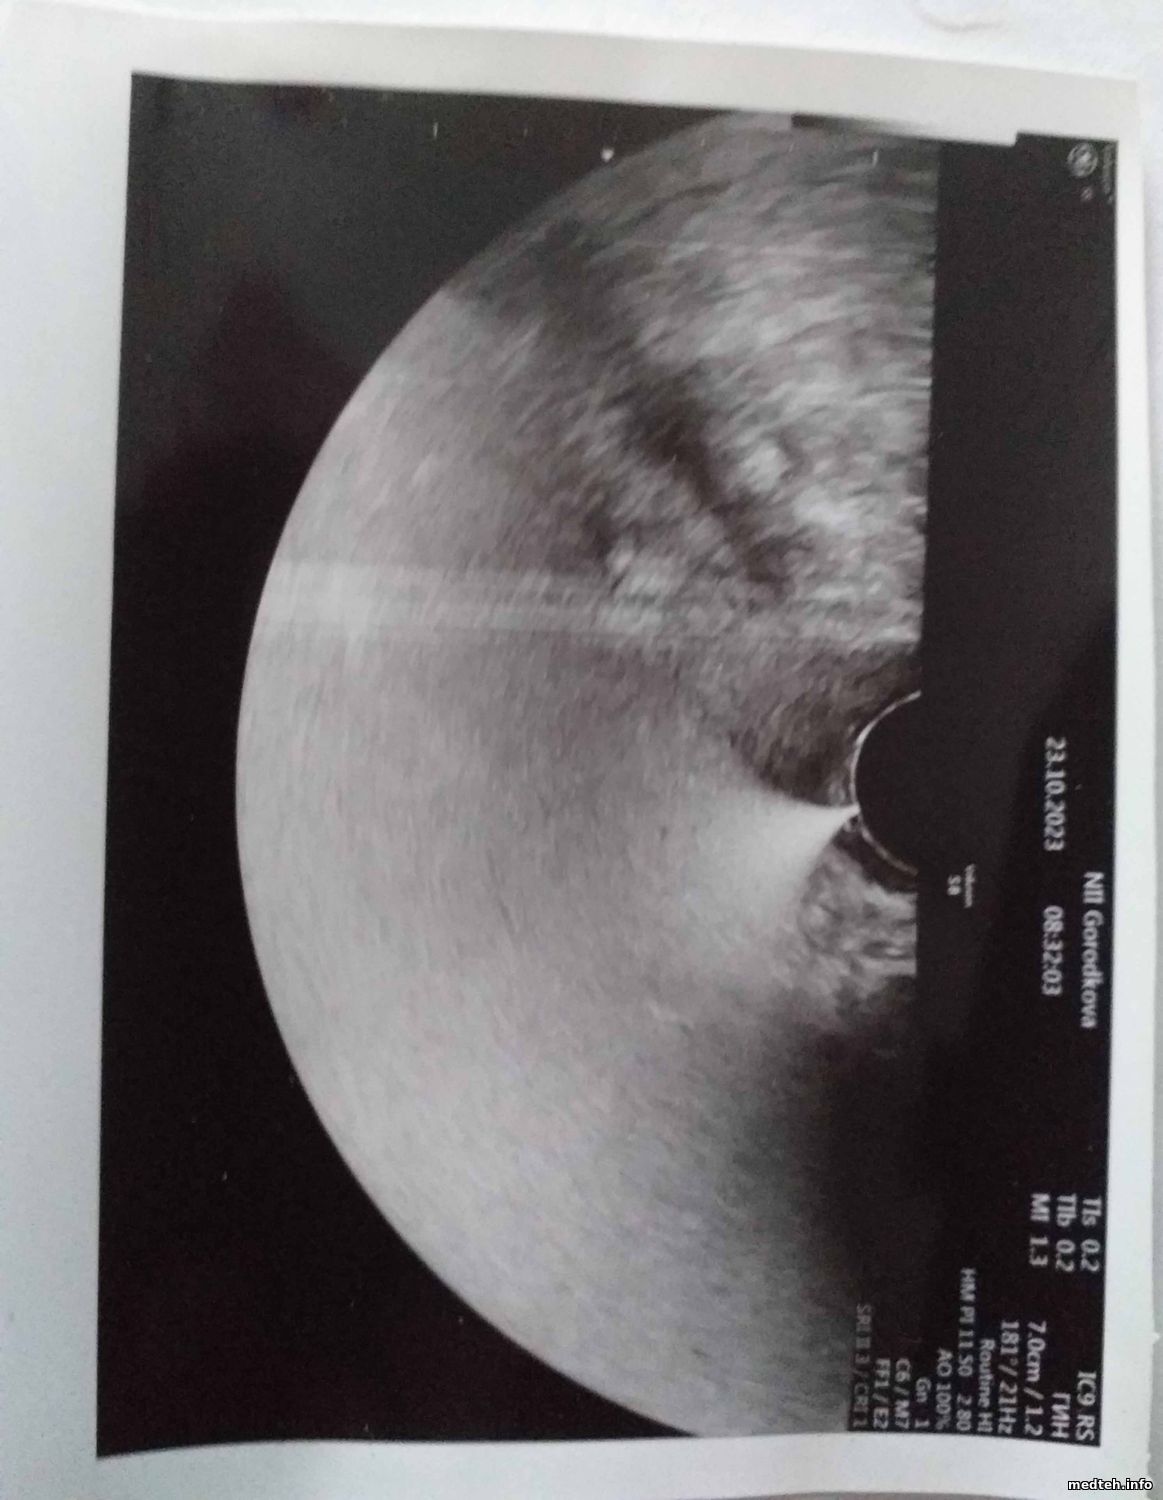

Товарищи, помогите разобраться: на УЗИ появились помехи (на фото видно).

Проверял напряжение на плате бимформер (в норме), менял конденсаторы (не помогло).

Потом появилась идея - скорее всего, гадит такую помеху FPGA чипы (два больших на плате Altera stratix III). Прогрел чип феном с нижним подогревом и флюсом - проблема УШЛА полностью, но всего на месяц, потом помехи возобновились.

Принял плату опять на диагностику, и сделал рентгеновский снимок чипов FPGA (на фото видно) на них увидел слияния некоторых шаров под чипом, но вот не знаю - должно ли так быть, или это заводские замыкания, которые нужны для работы?

Если это брак, то как тогда плата вообще работала с такими замыканиями несколько лет?

Надо ли делать ребол в таком случае, или опять пробовать жарить плату?

5990871.jpg (98.3 Kb) · 4719589.jpg (65.3 Kb) · 3714070.jpg (261.9 Kb) · 1562604.jpg (251.0 Kb) · 3824746.jpg (216.1 Kb)